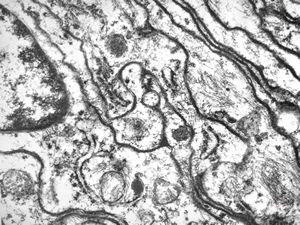

F,13y. | n.suralis … axonal neuropathy … Charcot-Marie-Tooth disease